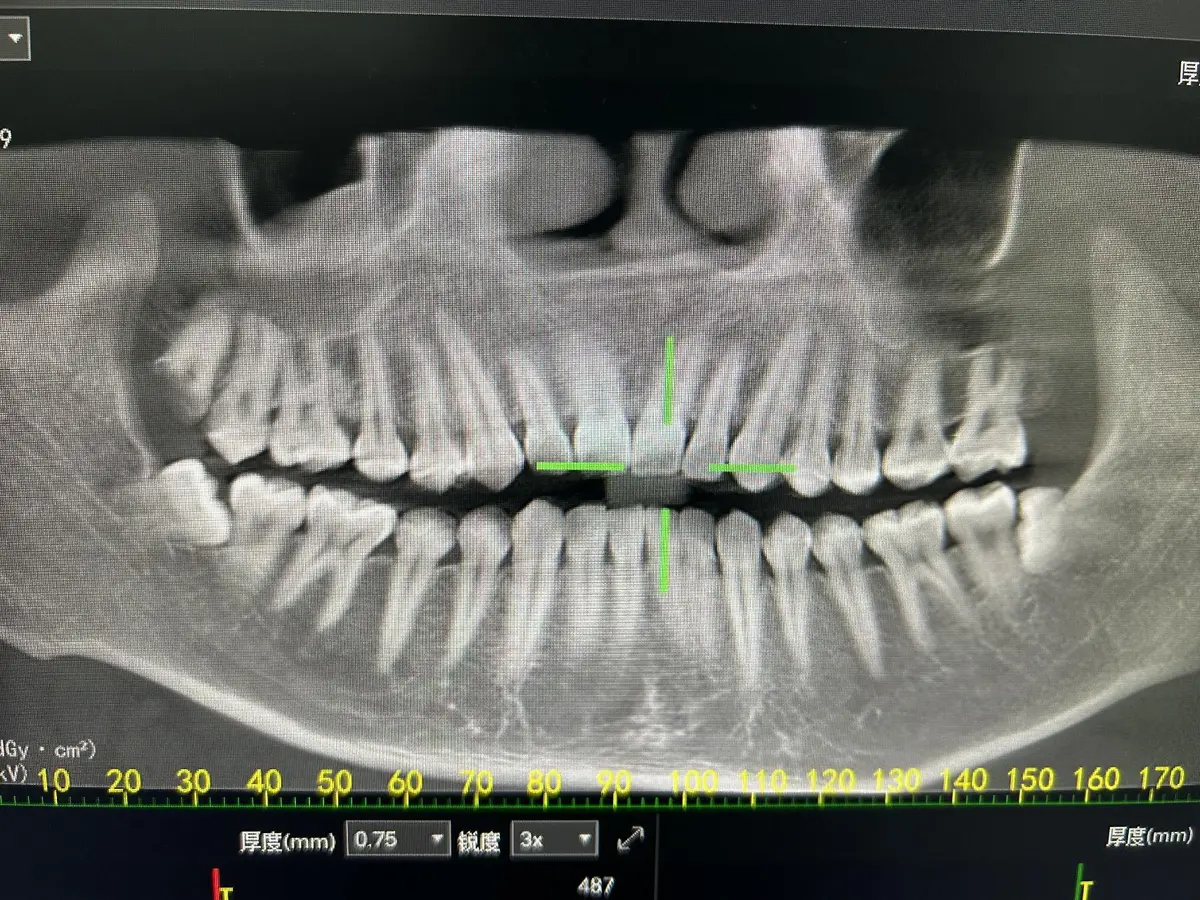

上排最右边的智齿早就烂得只剩半个牙了。之前因为甲亢数据不稳定,一直不敢去拔。

这次没约到江医生的号,约到了副主任尹医生的,下午两点半稍微等了会儿就叫到我了。医生一看,说有五颗牙要补,尤其是右上角最边上那颗,蛀得特别厉害,说大概率要做根管,先试着补一下,要是之后还痛再回来做根管。

这天去拆线,咨询了医生剩最后一个智齿该怎么拔。下排最左边还有一颗智齿,应该是挺不好拔的说有点弯,江医生让我下次约主任或者副主任的号或者直接去约医院的号,他拔不了。想着社保统筹的钱不是很多了,还得去做甲亢复查,加上拔比较深的智齿会痛的比较久,打算26年1月份再去拔,到时候再仔细想想是去医院拔还是社康约主任的号。